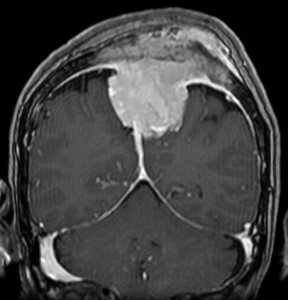

上矢状洞髄膜腫 superior sagittal sinus meningioma

上矢状洞を埋め尽くすように増大して,頭蓋骨浸潤が著しい髄膜腫ですが,ごく軽度の右足脱力以外に何の症状もありません。上矢状洞はゆっくり閉塞すれば,このような頭頂部から後頭部にわたる広範閉塞でも,静脈還流に障害がない場合が多いといえます。大脳の前半部の血流は前頭葉表面の皮質静脈から海綿静脈洞に側副路を形成しています。頭蓋内圧亢進所見もなく,これらはこの髄膜腫がゆっくり増大したということを示唆しています。

手術直後の画像です。全部いっぺんに摘出するのは無理なので,まず前から80%くらいの腫瘍を摘出しました。肥厚した骨はチタンプレートで置き換えてあります。後頭部の上矢状洞内と大脳鎌に少し残りましたが,この6ヶ月後に2回目の開頭術をして全摘出しました。結果的にこの例では,上矢状洞を冠状縫合のあたりから,静脈洞交会まで壁ごと全部摘出しましたが,脳浮腫も何も生じませんでした。腫瘍の両側にある皮質静脈 cortical veinsを損傷しないことが肝要です。

右の病理像は,頭蓋骨浸潤している部分 ですが,骨破壊は良性髄膜腫に特徴的な骨内浸潤像です。この骨浸潤像は悪性像とはいえません。MIB-1は高いところで8%、低いところで3%程度です。